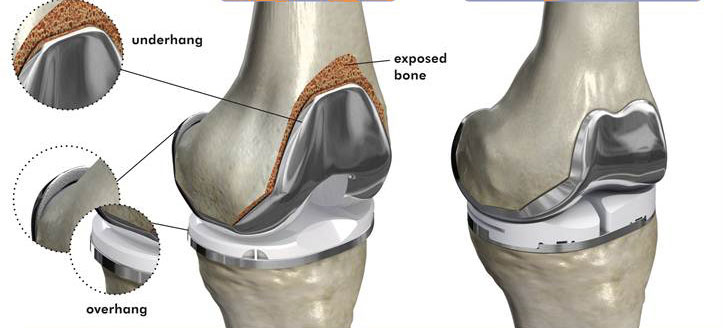

Knee replacement surgery, also known as arthroplasty, is a procedure that aims to reduce or eliminate knee pain by removing damaged or diseased parts of the knee bones and replacing them with an artificial one made of metal or plastic. An orthopedic surgeon performs this procedure.

Carefully, the damaged portions of your knee joint, including damaged bone and cartilage, are removed.

Step 4: Implant Placement

Artificial components, known as implants, are inserted. These implants can be made from metal, plastic, or a combination of both, closely resembling the form and function of a healthy knee joint.

Step 5: Attachment

The implants are securely attached to your bone, using special cement or press-fit techniques. This ensures they take on the role of a natural knee joint effectively.